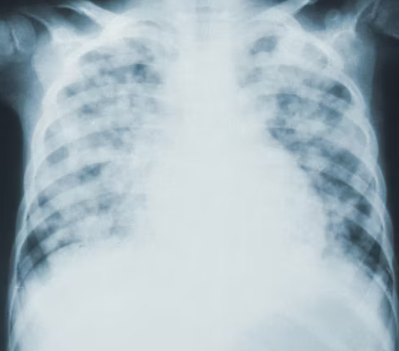

⚠️ 천식을 놓치기 쉬운 초기 증상

천식은 증상이 갑자기 나타났다가 저절로 또는 약물 사용 후 좋아지는 특징이 있습니다. 초기에는 감기나 단순 기침으로 오인하기 쉬워 진단이 늦어지는 경우가 많습니다. 다음과 같은 증상들이 반복되거나 특정 상황에서 나타난다면 천식을 의심해 볼 수 있습니다.